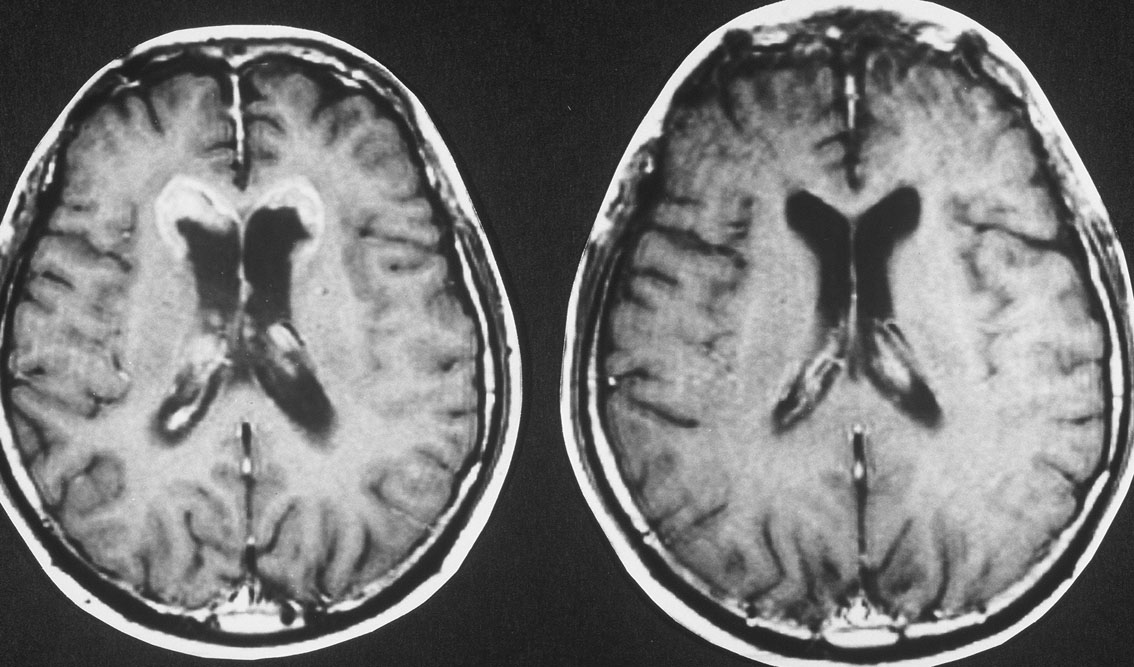

脳室上衣下浸潤(剖検例)

subependymal infiltration (autopsy)

11歳(1977年)で発症して放射線治療を受け,21歳(1987年)で再発しました。側脳室の前角にガドリニウム増強される典型的なgerminomaの再発像がみれます。脳表にも脊髄にも髄液播種はありませんでした。

CDDP/VP-16化学療法で腫瘍は消失し,放射線治療を加えました。

2度目の再発です。側脳室の壁に再発したので,また化学療法をしましたら,右の画像のようにきれいに消えました。この時点でも髄液吸収障害性水頭症にも閉塞性水頭症にもなっていません。

3度目の再発です。また脳室の壁から再発しました。化学療法で腫瘍はまた消失しました。その後も維持化学療法を行ったのですが,脳室内再発が止められず,第4脳室底部の腫瘍が延髄に浸潤して死亡しました。

最後まで水頭症はありません。